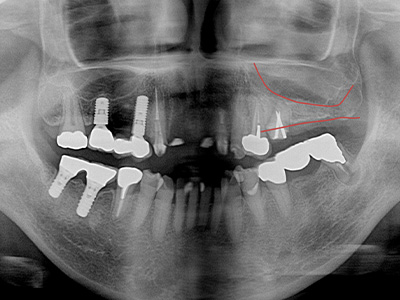

サイナスリフト

(ラテラルアプローチ)上顎の奥歯部分で骨の高さが不足している場合に行います。上顎洞の側面から骨を持ち上げ、骨補填材を入れて骨を増やします。手術後、 約6ヶ月で骨が再生され、インプラント治療が可能になります。